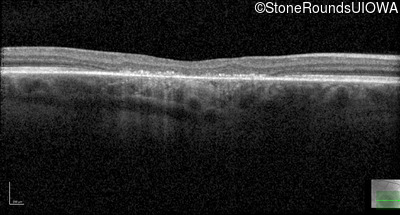

Age at visit: 17 years

This 17 year old male was correctable to 20/30 OU when he got his first glasses at age 5. At age 13 his best corrected vision was 20/40 OU. He feels that his color vision has always been poor.

Age at visit: 17 years (Visit 2)

Age at visit: 21 years

Age at visit: 23 years

Age at visit: 25 years